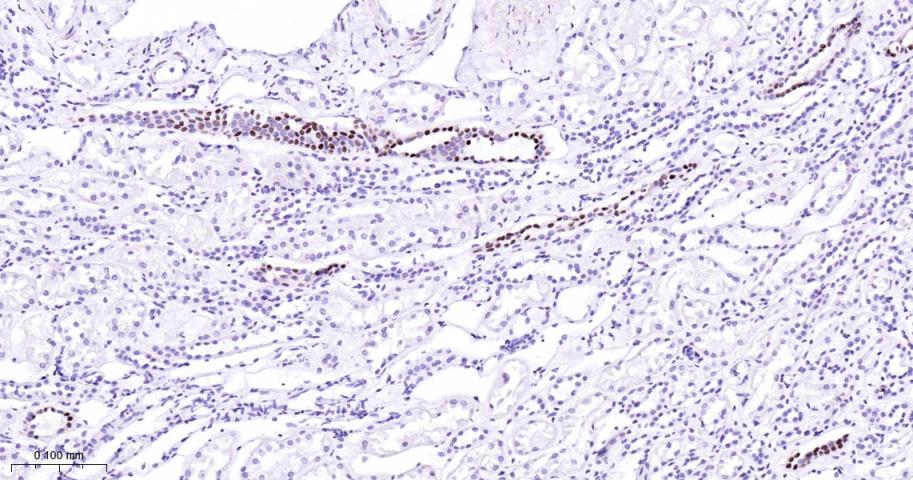

Paraformaldehyde-fixed, paraffin embedded Human kidney; Antigen retrieval by boiling in sodium citrate buffer (pH6.0) for 15 min; Antibody incubation with GATA3 Monoclonal Antibody, Unconjugated(bsm-60794R) at 1:200 overnight at 4°C, followed by conjugation to the bs-0295G-HRP and DAB (C-0010) staining.